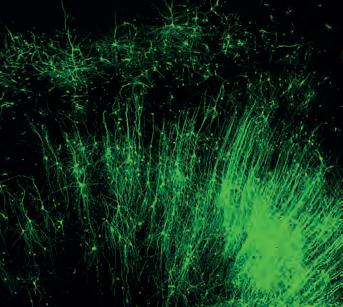

Duke University researchers have developed an RNAbased editing tool that targets individual cells, rather than genes.

It is capable of precisely targeting any type of cell and selectively adding any protein of interest.

Researchers said the tool could enable modifying very specific cells and cell functions to manage disease.

Using an RNAbased probe, the team demonstrated they can introduce into cells fluorescent tags to label specific types of brain tissue – a light-sensitive on/off switch to silence or activate neurons of their choosing; and even a self-destruct enzyme to precisely expunge some cells, but not others.

Neurobiologist Josh Huang said. “We could actually modify specific types of cell function to manage diseases, regardless of their initial genetic predisposition. That’s not possible with current therapies or medicine.”

go.nature.com/3fvTTEr